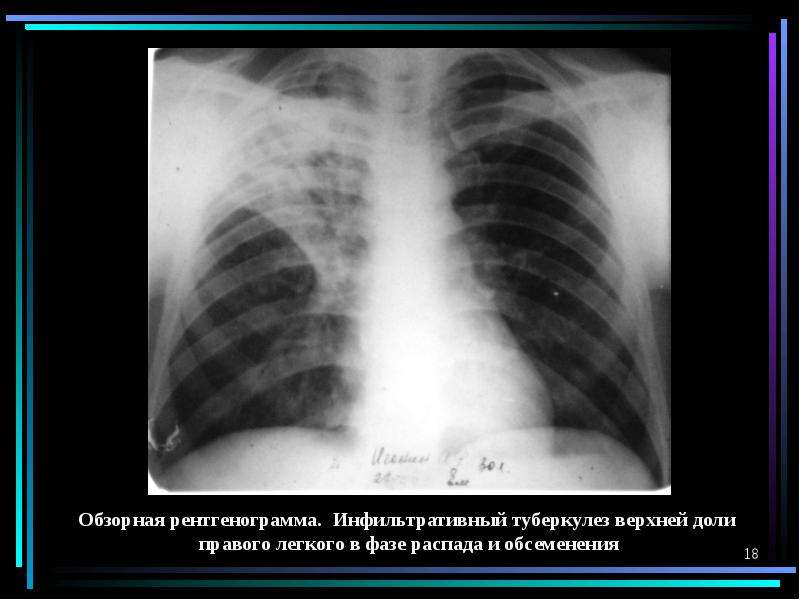

Очаговый и инфильтративный туберкулез презентация - 94 фото